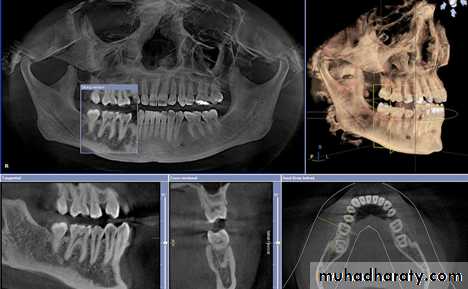

THE ADVENT OF CBCT AND THE THIRD PLANE OF VISUALIZATON

CBCT has been optimized for dental applications. Smaller fields of view and higher resolution scans appear to be ideal for endodontic use and may impact the nature of endodotic practice and radiographic decision-making in the near Future. One of the disadvantages of CBCT use is cost and access to the technology. However, with time, costs should continue to decrease and access to increase

A major advantage of CBCT is the visualization of anatomic

structures in three planes, generally referred to as coronal, axial (transverse), and sagittal reconstructions. CBCT technology also allows for panoramic and oblique reconstructions in addition to anatomic-specific reformatting such as temporomandibular joint (TMJ) improved the sensitivity and specificity of accurately detecting lesions or conditions affecting the jaws

Currently, CBCT imaging is generally recommended for endodontic cases in which conventional dental radiographs may not yield adequate information